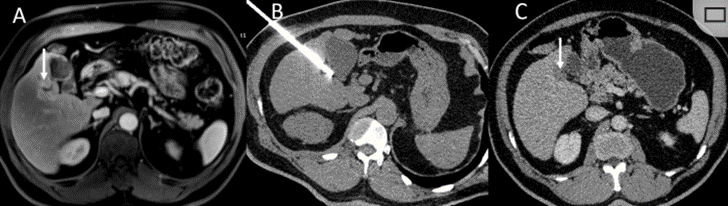

62歲女性,肝轉(zhuǎn)移(卵巢癌)腫瘤的完全消融病例

(a)軸向CT顯示病變位置毗鄰心臟和上腔靜脈(黑色箭頭)。

(b)術(shù)中軸向CT掃描:使用三個(gè)冷凍探針。

(c)冠狀面和(d)矢狀面顯示冰球毗鄰心包。

1個(gè)月后的軸向(e)和冠狀位(f)增強(qiáng)CT掃描顯示低密度區(qū)域,由于肉芽組織反應(yīng)引起的邊緣增強(qiáng)。